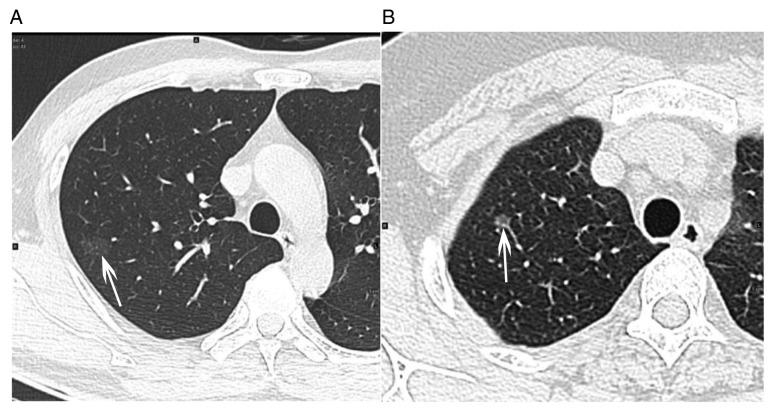

采用非增强和对比增强CT纹理分析识别表现为磨玻璃密度结节的肺腺癌:一项回顾性分析。

Pulmonary adenocarcinoma appearing as ground-glass opacity nodules identified using non-enhanced and contrast-enhanced CT texture analysis: A retrospective analysis.

The present study aimed to investigate the ability of CT-based texture analysis to differentiate invasive adenocarcinoma (IA) from pre-invasive lesions (PIL) or minimally IA (MIA) appearing as ground-glass opacity (GGO) nodules, and to further compare the performance of non-enhanced CT (NECT) images with that of contrast-enhanced CT (CECT) images. A total of 77 patients with GGO nodules and surgically confirmed pulmonary adenocarcinoma were included in the present retrospective study. Each GGO nodule was manually segmented and its texture features were extracted from NECT and CECT images using in-house developed software coded in MATLAB (MathWorks). The independent-samples ttest was used to select the texture features with statistically significant differences between IA and MIA/PIL. Multivariate logistic regression and receiver operating characteristics (ROC) curve analyses were performed to identify predictive features. Of the 77 GGO nodules, 12 were atypical adenomatous hyperplasia or adenocarcinoma (15.6%), 36 were MIA (46.8%) and 29 were IA (37.7%). IA and MIA/PIL exhibited significant differences in most histogram features and gray-level co-occurrence matrix features (P<0.05). Multivariate logistic regression and ROC curve analyses revealed that smaller energy and higher entropy were significant differentiators of IA from MIA and PIL, irrespective of whether NECT images [area under the curve (AUC): 0.839, 0.859] or CECT images (AUC: 0.818, 0.820) are used. Texture analysis of CT images, regardless of whether NECT or CECT is used, has the potential to distinguish IA from PIL or MIA, particularly the parameters of energy and entropy. Furthermore, NECT images were simpler to obtain and no contrast agent was required; thus, analysis with NECT may be a preferred choice.

摘要